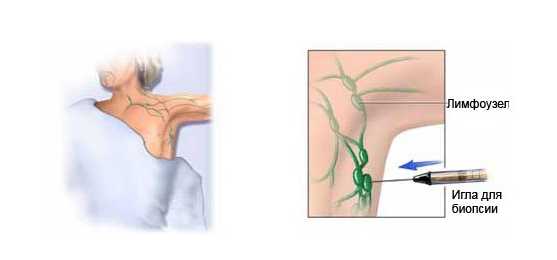

УЗИ лимфоузлов при лимфоме Ходжкина

Раздел: Образы вокруг